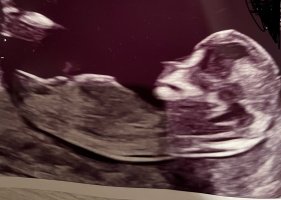

Blir en liten jente jaHva tror dere? Har følelsen på jente men vet ikke med nubben..

Kan legge til at bildene ble tatt da jeg var 12 + 6God kveldEr det noen som klarer å tyde kjønn fra disse bildene? Jeg synes dette er for vanskelig selv og jeg er så fryktelig spent. På forhånd takk

Er ikke ofte man ser et så bra bilde av nub, Så her ser man kjønnet godt og det er ingen tvil.

På bildet jeg legger ved ser du tydelig de to strekene på jente, mens en gutt i uke 13 ville stått opp med stacking.